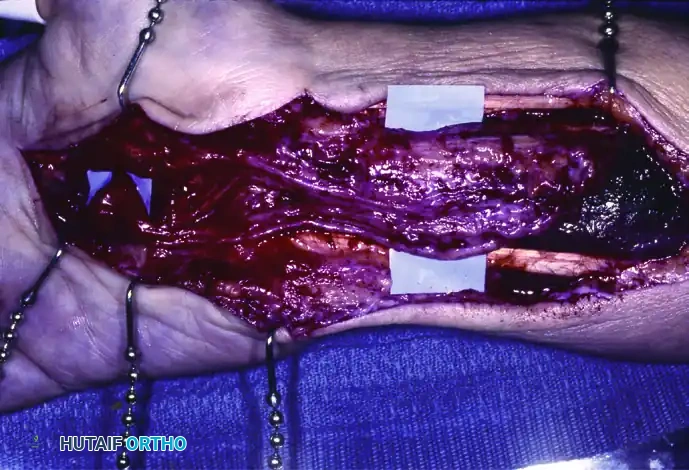

Extensive involvement of the median nerve coursing from the distal third of the forearm into the palm, demonstrating massive fibrofatty hypertrophy.

A closer intraoperative view of severe enlargement of the median nerve. Note the loss of normal fascicular architecture due to infiltration.